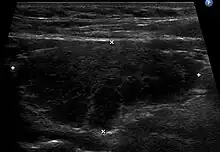

Ultrasound imaging of the thyroid gland (right lobe longitudinal) in a person with Hashimoto thyroiditis

Diagnosis is usually made by detecting elevated levels of antithyroid peroxidase antibodies in the serum, but seronegative (without circulating autoantibodies) thyroiditis is also possible.[54] An ultrasound may be useful in detecting Hashimoto thyroiditis, especially in those with seronegative thyroiditis, due to key features detected in the ultrasound of a person with Hashimoto's thyroiditis, such as "echogenicity, heterogeneity, hypervascularity, and presence of small cysts."[55]

Ultrasound

Ultrasound imaging of the thyroid showing Hashimoto's thyroiditis

When patients have normal laboratory values but symptoms of autoimmune thyroiditis, ultrasound plays a role in diagnosis.[16] Images obtained with ultrasound can evaluate the size of the thyroid and further support the diagnosis of autoimmune thyroiditis, reveal the presence of nodules, or provide clues to the diagnosis of other thyroid conditions.[16]